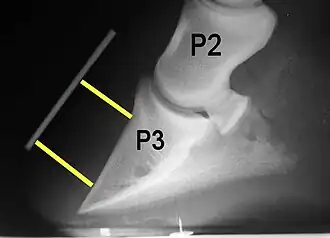

Radiographs are an important part of evaluating the laminitic horse. They not only allow the practitioner to determine the severity of the episode, which does not always correlate with degree of pain,[1] but also to gauge improvement and response to treatment. Several measurements are made to predict severity. Additionally, radiographs also allow the visualization and evaluation of the hoof capsule, and can help detect the presence of a lamellar wedge or seromas.[1] The lateral view provides the majority of the information regarding degree of rotation, sole depth, dorsal hoof wall thickness, and vertical deviation.[1][17] A 65-degree dorsopalmar view is useful in the case of chronic laminitis to evaluate the rim of the coffin bone for pathology.[1]

Several radiographic measurements, made on the lateral view, allow for objective evaluation of the episode.

- Horn:lamellar distance (HL): the measurement from the most superficial aspect of the dorsal hoof wall to the face of P3. 2 distances are compared: a proximal measurement made just distal to the extensor process of P3, and a distal measurement made toward the tip of P3. These two values should be similar. In cases of rotation, the distal measurement will be higher than the proximal. In cases of distal displacement, both values will increase, but may remain equal. Therefore, it is ideal to have baseline radiographs for horses, especially for those at high-risk for laminitis, to compare to should laminitis ever be suspected. Normal HL values vary by breed and age:[1]